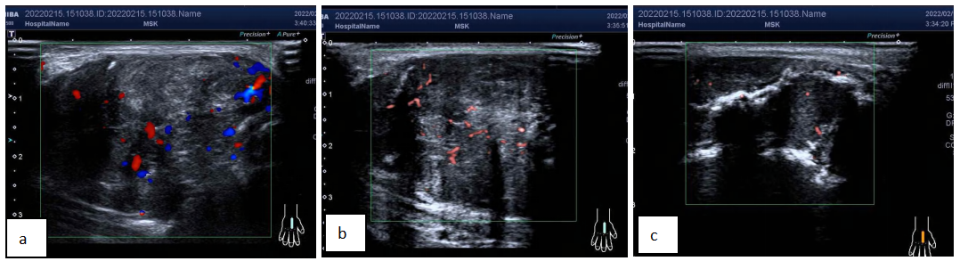

右手 MRI 提示右手第 3 掌骨骨质破坏伴周围软组织肿块,考虑骨肿瘤,恶性可能性大,请结合临床。

图片图 5 右手 MRI 可见右手第 3 掌骨骨质破坏,周围见软组织肿块影